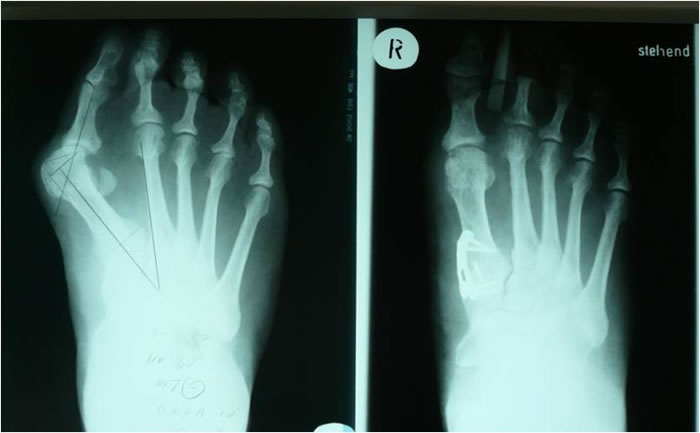

Die Fußchirurgie ist in den letzten Jahren einem erheblichen

Wandel unterworfen. Die verschiedenen operativen Vorgehensweisen

in der Fußchirurgie profitieren heute von speziellen

Materialien zur Fixation (Schrauben, winkelstabile Platten,

Implantate aus Titan etc.) und führen auch durch schonende

Narkosetechniken (Regionalanästhesien) und gezielte Physiotherapie

nach Operation zur schnellen Belastbarkeit des Fußes

und damit zu einem zügigem Heilverlauf und kürzeren

Arbeitsunfähigkeitszeiten.